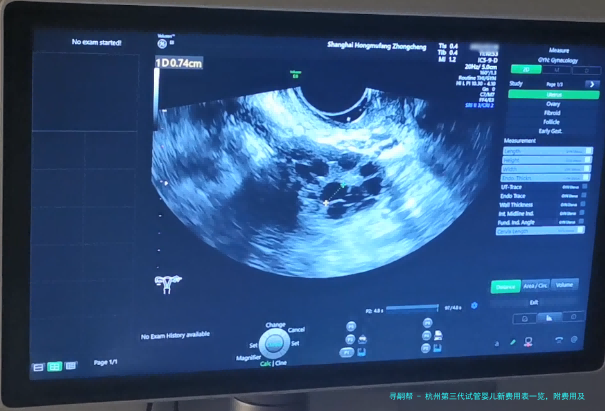

为了提高试管婴儿的成功几率,需要在此前做好相关的身体检查,防止有不利于试管婴儿操作的因素存留。两边的主要检查项目存在:血检、甲状腺整套功能、性激素六项检查、子宫B超检查、阴道分泌物检查、HPV检查、支原体检查、衣原体检查、卵巢功能评估AMH检查、精液常规检查等。